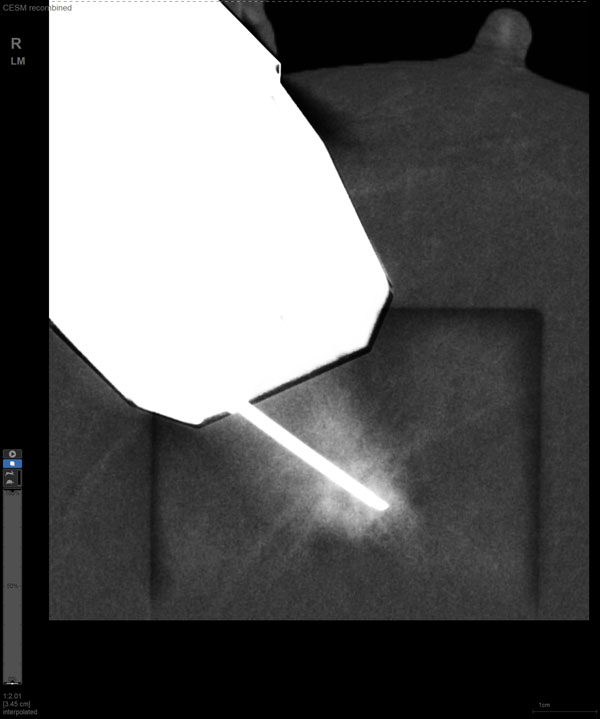

某患者增强磁共振成像MRI显示肿瘤周边有活性,中心区域有组织坏死。为得到准确的病理结果,穿刺靶区需避开肿物坏死区域。在与患者主管医生充分讨论后,放射科医生为患者行CEM引导下穿刺活检术。术中,CEM检查肿物同样显示为环形强化,巧妙避开坏死区域后,穿刺靶区选择了肿物增强早期明显强化区域,术程顺利,仅用时15分钟。术后该患者病理结果为浸润性导管癌Ⅱ级。

随着计算机技术发展和乳腺X线机硬件的提升,CEM与立体定向活检技术相结合的CEM引导下穿刺活检术开始在临床应用。与MRI引导的乳腺穿刺活检相比,CEM穿刺活检无需抗核磁耗材,成本更低,检查速度更快。据国外研究文献报道,CEM引导的穿刺活检有可能成为MRI引导的乳腺穿刺活检的有效替代方案。